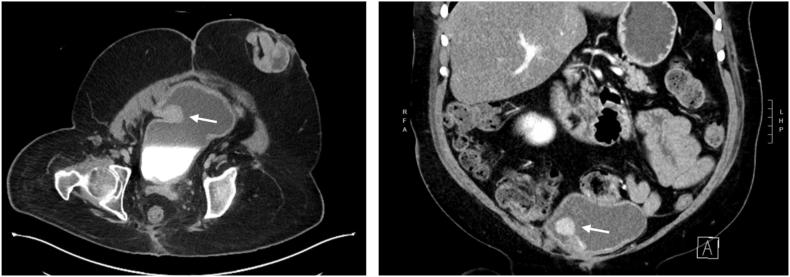

Patients with spina bifida are at increased risk of developing malignancy in the native or augmented bladder and tend to present with more advanced disease. Surgical guidelines for oncologic resections in patients with augmented bladders are not well described. Furthermore, there is limited knowledge regarding the changes in lymphatic drainage after bladder reconstruction. Herein we describe the case of a 45-year-old male with spina bifida who underwent gastrocystoplasty and developed adenocarcinoma of the augmented bladder segment 33 years later. We describe his surgical management with radical cystectomy and the use of sentinel lymph node dissection.